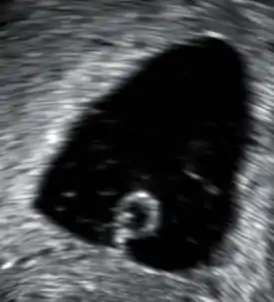

Выкидыш может быть обнаружен во время УЗИ или посредством серии замеров уровня хорионического гонадотропина человека (ХГЧ). Существуют медицинские способы для прекращения беременности с документально подтверждённой нежизнеспособностью плода, который не был изгнан естественным путём.

Выкидыш может быть обнаружен при помощи специальной ультразвуковой аппаратуры. При поиске микроскопических патологических симптомов выкидыша следует посмотреть снимок. К микроскопическим относятся ворсинки, трофобласт, части плода. Также можно выполнить генетические тесты для поиска ненормальных хромосом. Роль в морфологическом исследований заключается в выявлении и изучении морфологических изменений в материале получаемый при спонтанных абортах.

Потеря крови во время ранней беременности является наиболее распространённым симптомом. В случае потери крови и/или болей выполняется трансвагинальное УЗИ. Если с помощью ультразвука не установлена жизнеспособность внутриутробной беременности, то должны быть выполнены определённые тесты, чтобы исключить внематочную беременность, которая опасна для жизни.